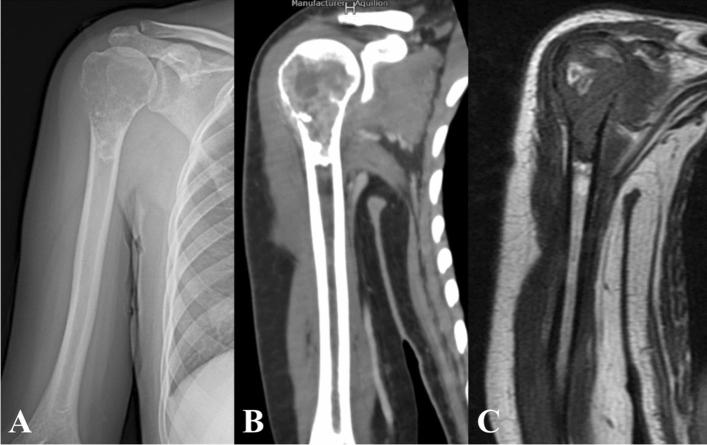

The purpose of this study was to evaluate the functional results, complications and related factors of prosthesis reconstruction after malignant tumor resection of primary proximal humeral, and also evaluate whether soft tissue reconstruction with mesh patch and anchors can improve clinical results. From 2002 to 2016, forty-one patients were enrolled in this study. The pathological diagnosis contained 27 cases of osteosarcoma, 7 cases of chondrosarcoma and other primary malignant bone tumors. Both mesh patch and anchors were used in the reconstruction of joint capsule and the surrounding soft tissues in 27 cases. The mean postoperative follow-up was 60.6 months. The average active abduction angle and passive abduction angle was 33.5 (5-71) degrees and 72.4 (52-104) degrees. The prosthetic humeral head displacement was over 2 cm in 5 cases (12.2%). The average MSTS score was 23.1. The overall 5-year survival rate of prosthesis was 88.2%. The length of osteotomy, whether preserving deltoid muscle, whether applying mesh patch and anchors had significant effects on the abduction angle of shoulder joint; the length of osteotomy, whether applying mesh patch and anchors had significant effects on the degree of upward displacement of prosthesis. The application of both mesh patch and anchors in prosthesis reconstruction achieved more stable result and better function of shoulder joint. To ensure the stability of shoulder joint and the firm wrapping of surrounding soft tissue are key factors affecting the postoperative function.

本研究旨在评估原发性肱骨近端恶性肿瘤切除后假体重建的功能结果、并发症及其相关因素,并评估网片和锚钉的软组织重建是否能改善临床结果。2002 年至 2016 年间,共纳入 41 例患者。病理诊断包括 27 例骨肉瘤、7 例软骨肉瘤等原发性恶性骨肿瘤。27 例患者同时使用网片和锚钉修复关节囊和周围软组织。术后平均随访 60.6 个月。术后平均主动外展角度和被动外展角度分别为 33.5(5-71)度和 72.4(52-104)度。5 例(12.2%)假体肱骨头移位超过 2cm。平均 MSTS 评分为 23.1。假体 5 年总体生存率为 88.2%。截骨长度、是否保留三角肌、是否应用网片和锚钉对肩关节外展角度有显著影响;截骨长度、是否应用网片和锚钉对假体向上移位程度有显著影响。假体重建中同时应用网片和锚钉可获得更稳定的结果和更好的肩关节功能。确保肩关节的稳定性和周围软组织的牢固包裹是影响术后功能的关键因素。